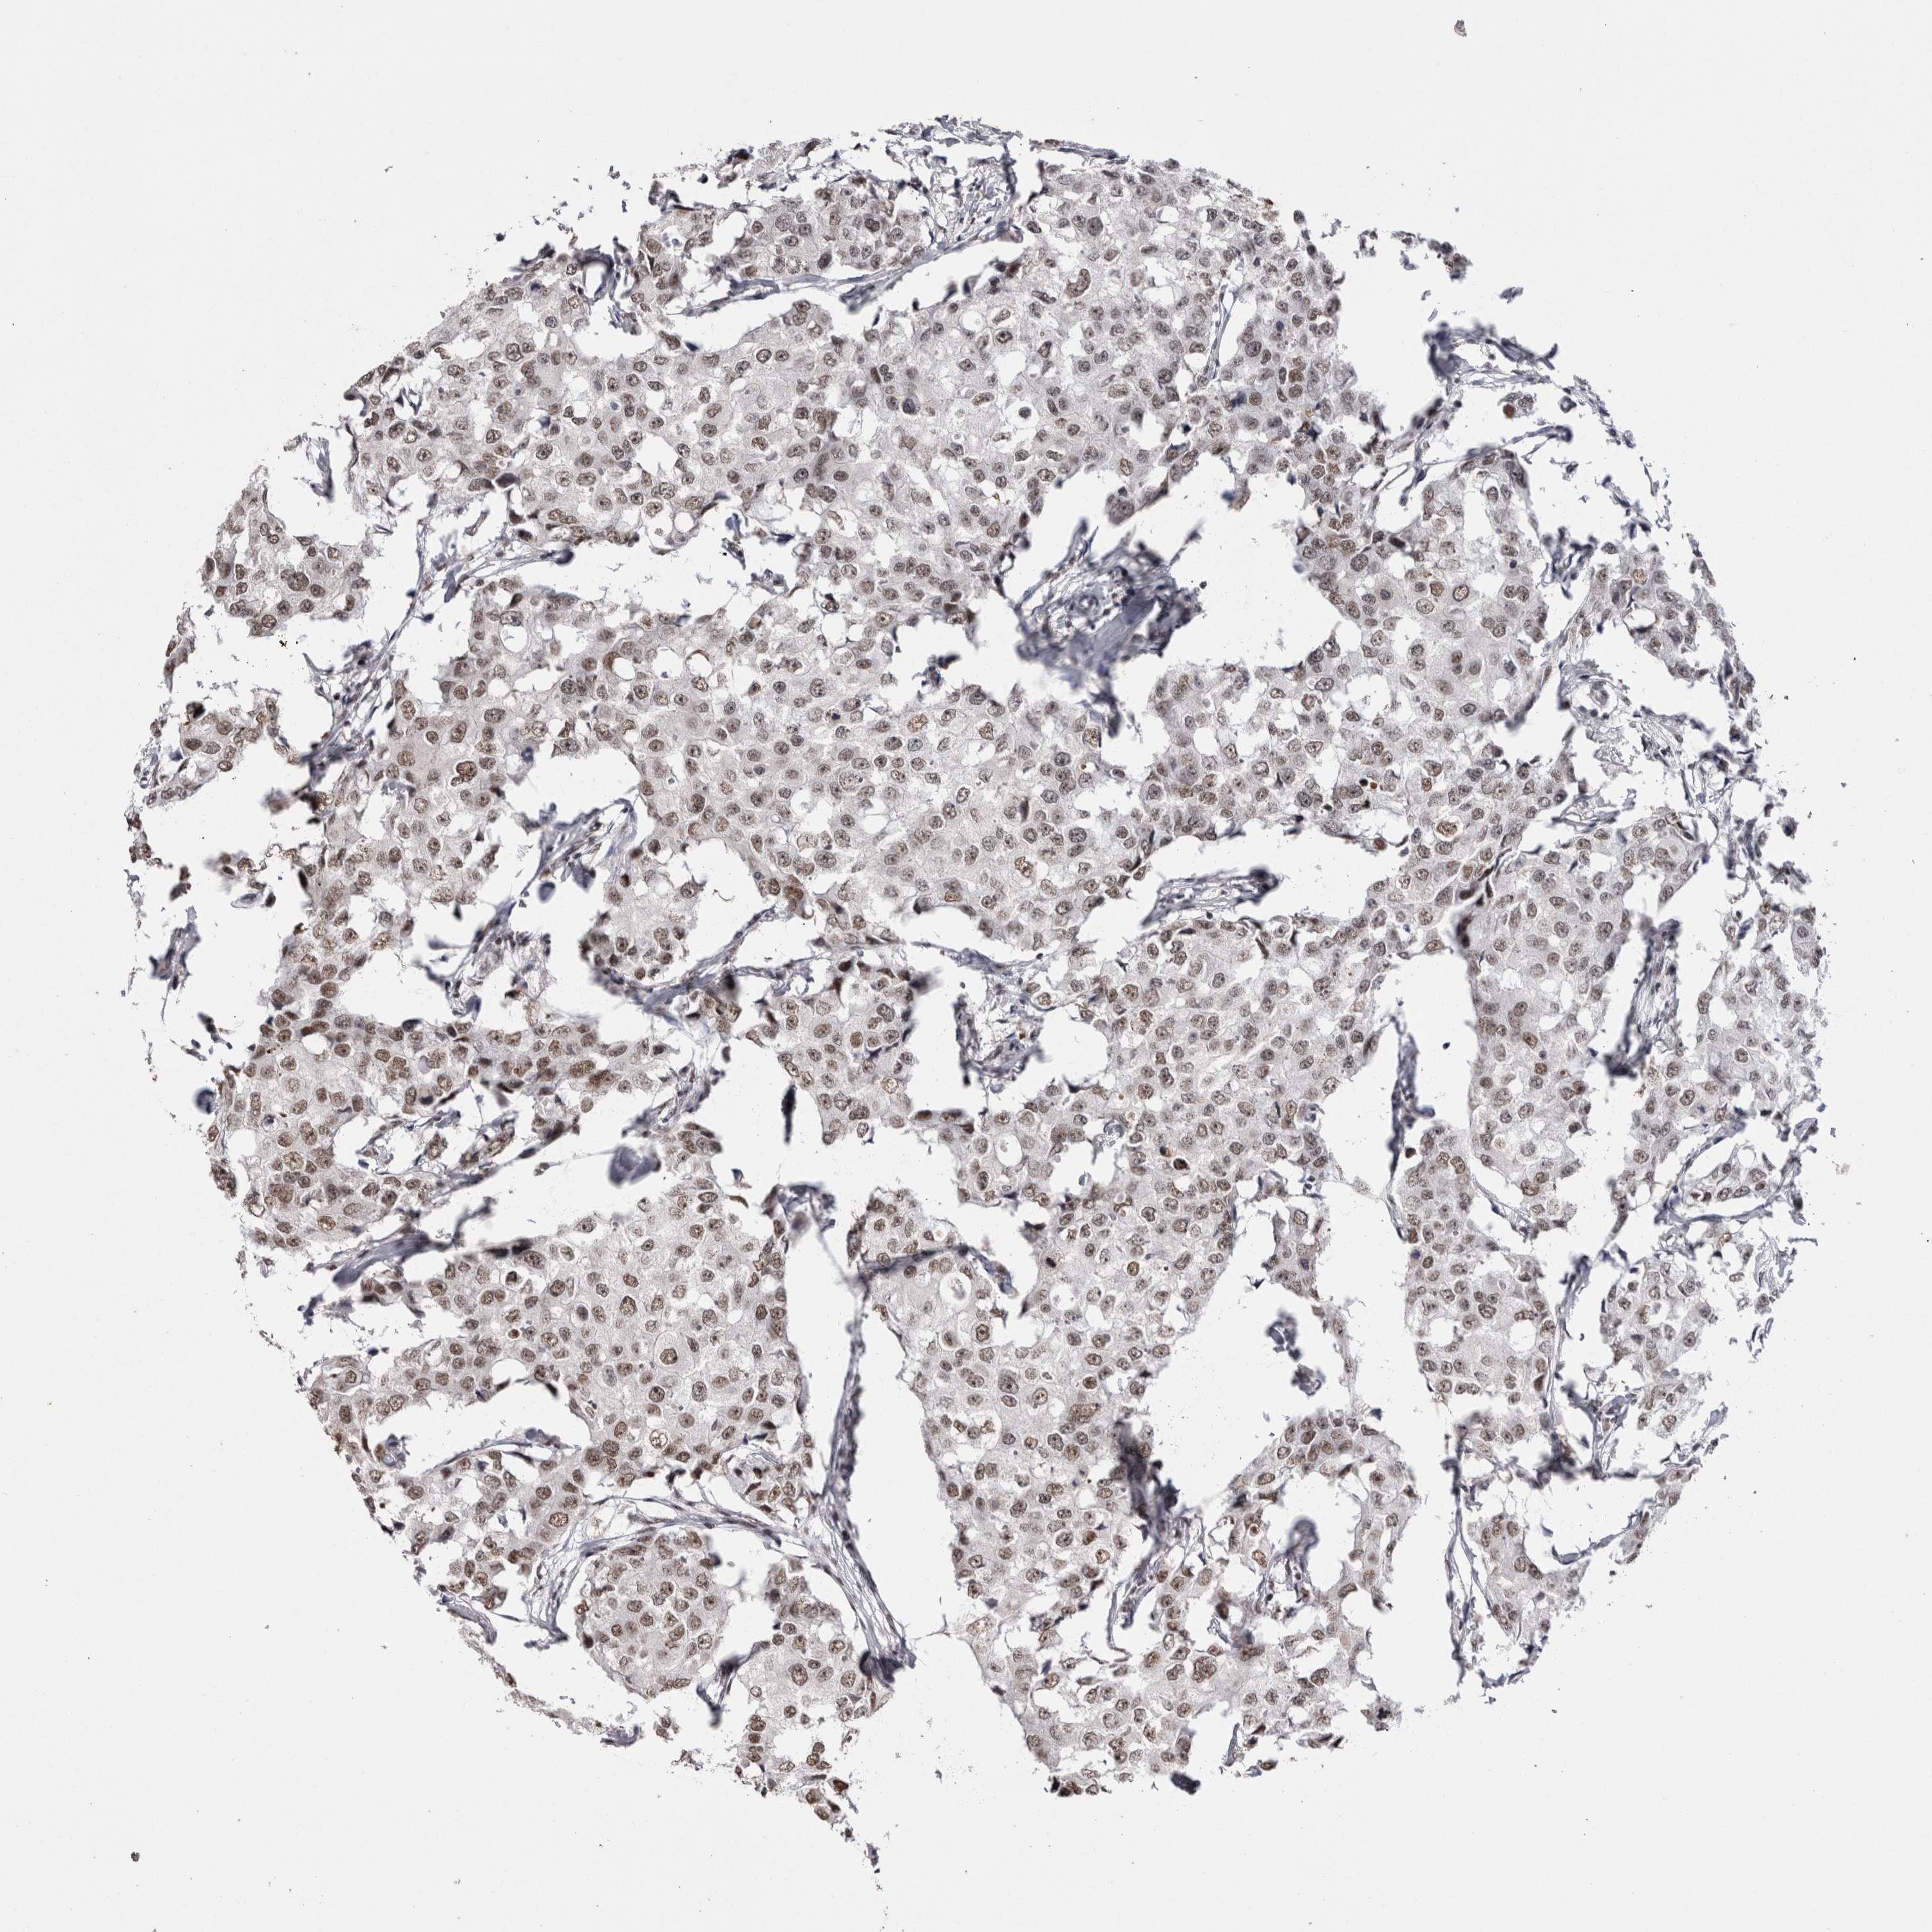

CANCER BREAST CANCER Show tissue menu

BRCA TCGA BRCA VALIDATION PROTEIN EXPRESSION